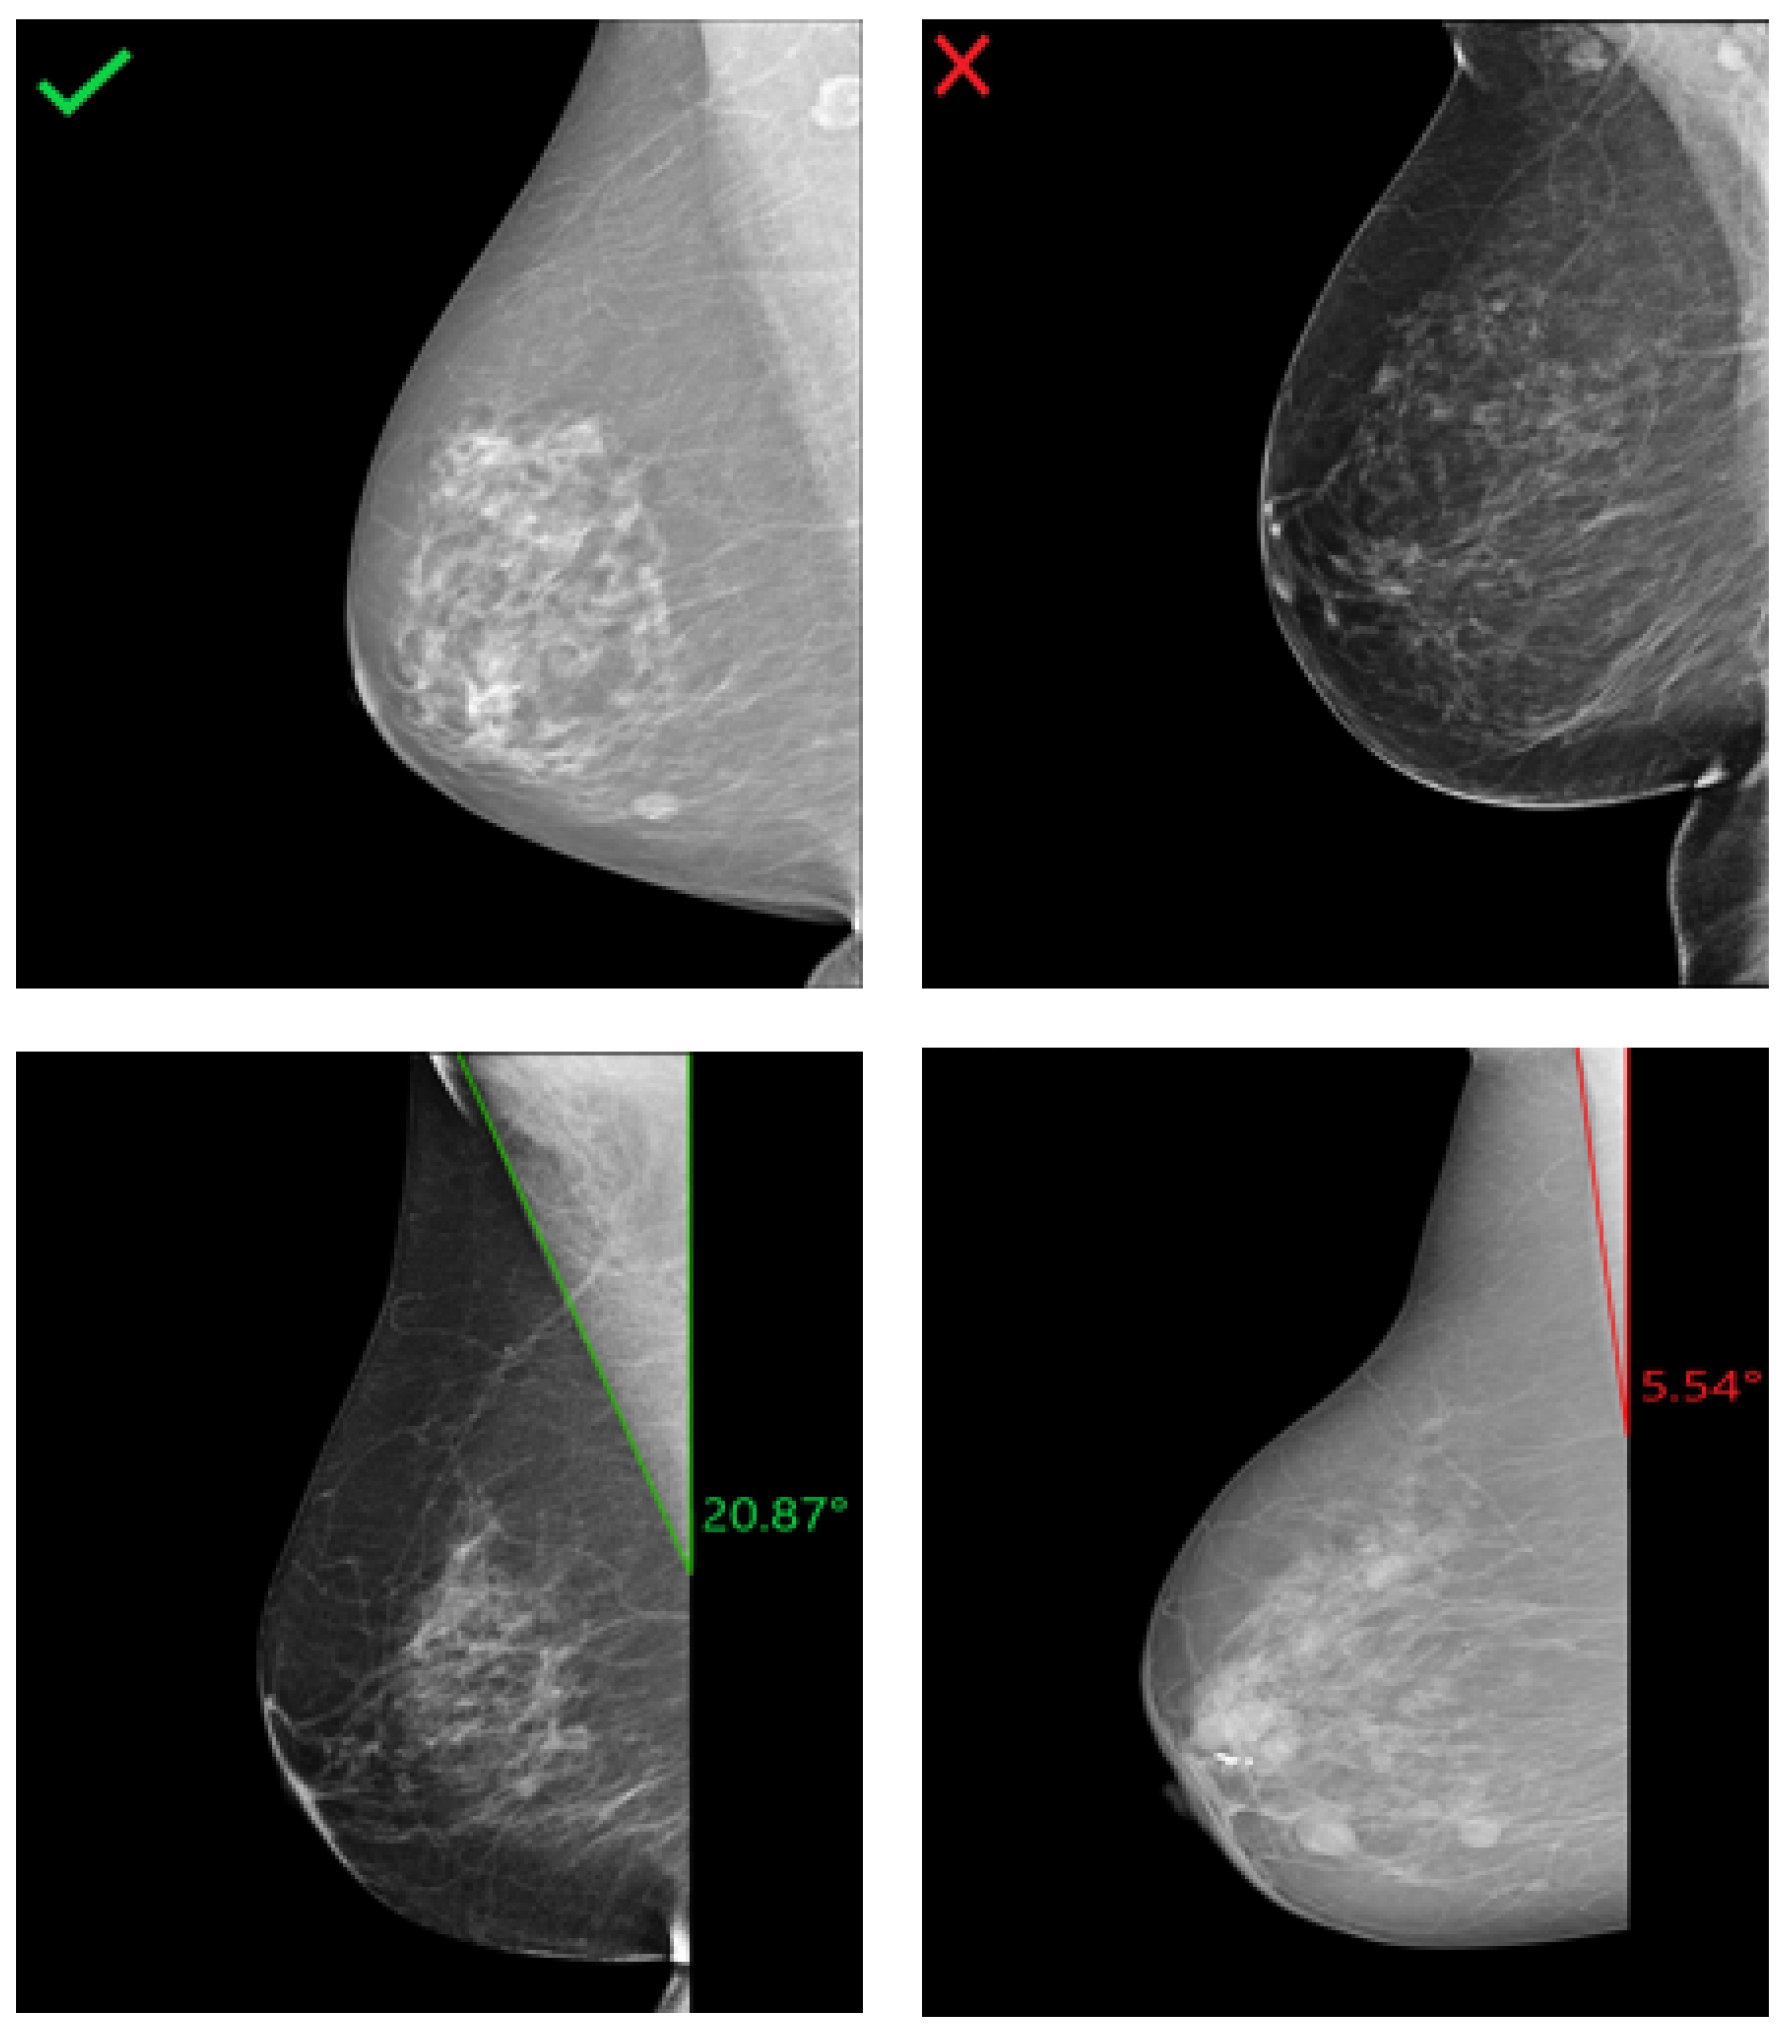

3.1. MLO: Pectoralis Muscle Angle